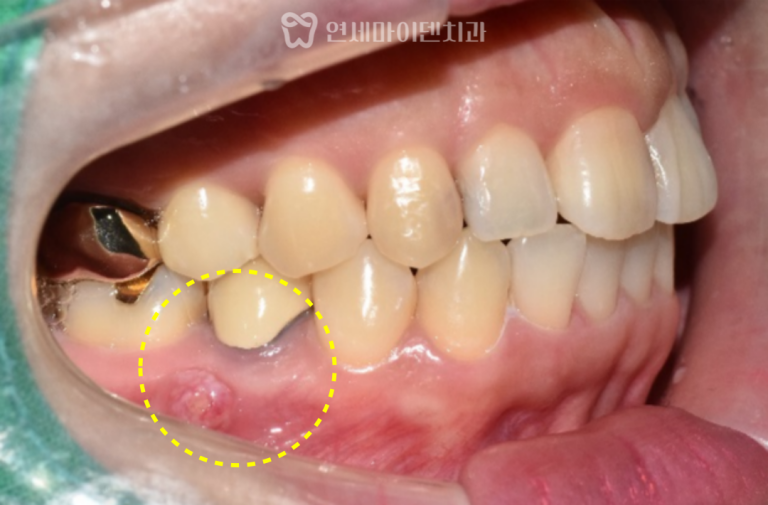

26번 치아 — 발치 즉시 임플란트

그러나 바로 뒤쪽의 #26번 치아는 상황이 달랐습니다.

보철물을 제거하자 내부에서 출혈이 계속되어 CT를 재확인했더니

구개측 뿌리(perforation)가 뚫린 상태였습니다.

염증으로 인해 주변 뼈 손실이 심했고,

수술은 뼈 보존을 고려해 즉시 식립 후

안정적으로 골유착을 유도하였고,

수술 부위의 잇몸도 건강하게 치유되었습니다.

임플란트 식립 한 달만에

식립 부위가 깨끗하게 아무는 것을 확인할 수 있습니다.